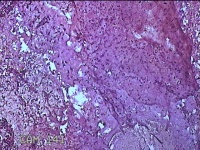

子宫腔内组织

性别

女

年龄

39岁

临床诊断

早期人工流产

一般病史

停经36天。

标本名称

大体所见

灰白暗红色不规则碎组织3x2.5x1.3cm一堆,未发现明显的绒毛样组织。

不具诊断价值。

在切片质量方面还需要加把劲。